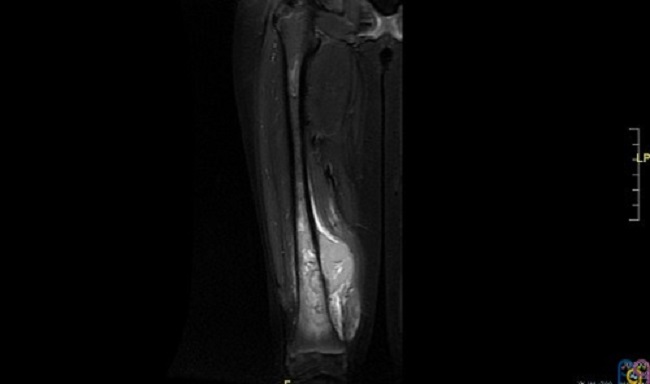

Se realiza traslado a hospital de referencia para ingreso en Unidad de Oncología. A su ingreso se amplía el estudio de la lesión realizando una resonancia magnética (Fig. 2 y Fig. 3) y estudio de extensión con tomografía computarizada pulmonar confirmándose la sospecha de tumor maligno óseo y metástasis pulmonares. Posteriormente se toma biopsia de dicha lesión guiada por ecografía confirmándose el diagnóstico de osteosarcoma.